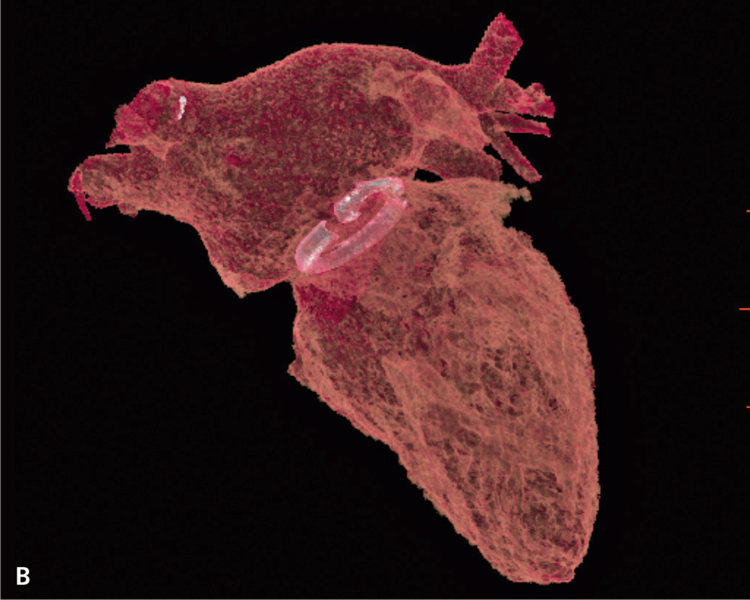

Po operacji wykonano kontrolne badanie TK serca, w którym nie stwierdzono zmian ogniskowych i zagęszczeń zapalnych w uwidocznionym miąższu płucnym. Przełyk oraz pozostałe uwidocznione badaniem struktury śródpiersia również były bez zmian. Uwidocznione węzły chłonne nie były powiększone. Badanie wykazało stan po plastyce przedsionka lewego oraz wszczepieniu sztucznego pierścienia w pierścień zastawki mitralnej. Objętość przedsionka po zabiegu wynosiła 129 cm3 (przed zabiegiem 186 cm3) (ryc. 1A, B, 2A, B).

RYCINA 2. Rekonstrukcja objętościowa (VR transparent) lewego przedsionka. [A] Przed operacją. [B] Po operacji.

Objętość późnorozkurczowa LK przed zabiegiem wynosiła 295 cm3, a po zabiegu 222 cm3 (ryc. 3A, B, 4A, B).

RYCINA 4. Rekonstrukcja objętościowa (VR transparent) jam serca lewego. [A] Przed operacją. [B] Po operacji.